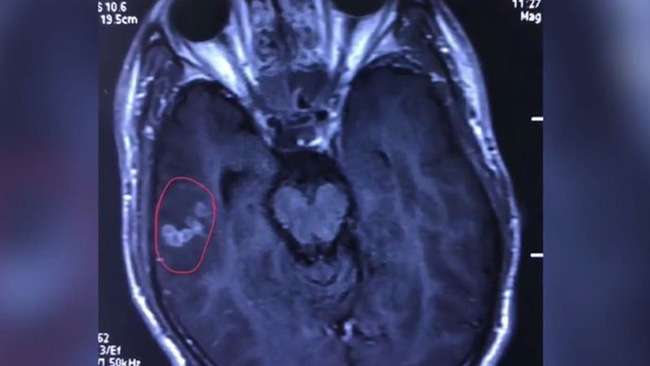

КИНЕСКИ хирурзи извадили су из мозга 26-годишњег пацијента пантљичару дугачку десет џцентиметара.

Како је објавио лист South China Morning Post, паразит је био откривен за време прегледа пацијента са презименом Лиу.

Према речима лекара Ванг Чунлијана, на присуство паразита је сигнализирала анализа крви. Потом је почела `потера` за њим.

Ванг је открио: „Црв је, када смо изгукли, још био жив. ради се о поврсти Spirometra mansoni“.